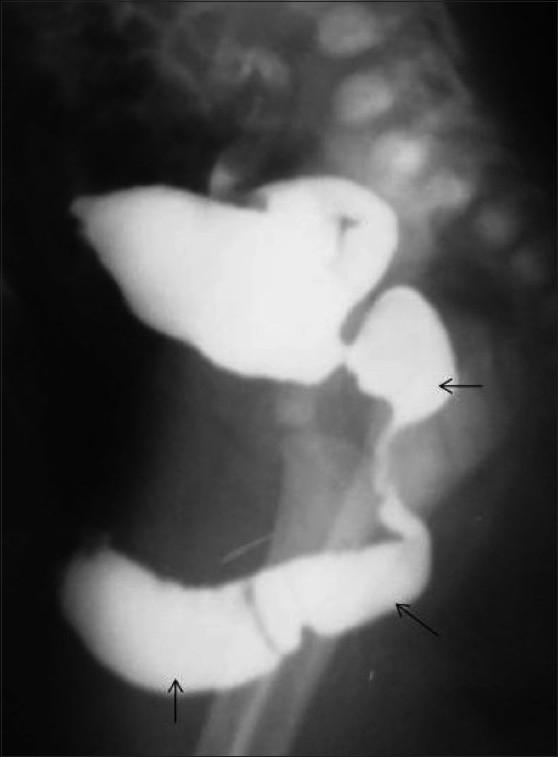

Congenital anomalies of the male urogenital tract are common. Some lesions like posterior urethral valve or anterior urethral diverticulum tend to present early in infancy and are often easily diagnosed on conventional contrast voiding cystourethrograms. Other conditions like posterior urethral diverticulum or utricle can be relatively asymptomatic and therefore present late in childhood. We present the spectrum of imaging findings of common and uncommon anomalies involving the male urethra. Since the pediatric radiologist is often the first to make the diagnosis, he or she should be well aware of these conditions.

男性泌尿生殖道先天性异常很常见。一些病变,如后尿道瓣膜或前尿道憩室,往往在婴儿期早期出现,通常在传统的排尿性膀胱尿道造影上很容易诊断。其他情况,如后尿道憩室或前列腺囊,可能相对无症状,因此在儿童期晚期出现。我们展示了涉及男性尿道的常见和罕见异常的影像学表现谱。由于儿科放射科医生往往是第一个做出诊断的人,他或她应该充分了解这些情况。